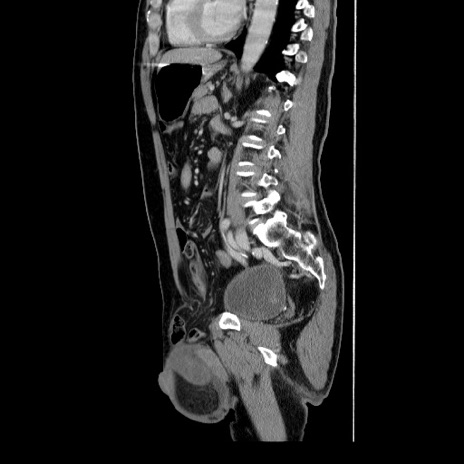

冠状断像

【症例】60歳代 男性

【主訴】右鼠径部膨隆

【現病歴】1年程前より右鼠径部膨隆あり。自己にて還納可能だったため放置していた。3時間前より右鼠径部の脱出を認め、還納困難となり受診。

【身体所見】右鼠径部に小児頭大の膨隆あり。弾性硬であり、用手還納は困難。左鼠径部にも膨隆を認める。脱出はなし。